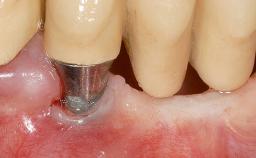

Soft-Tissue Volume Augmentation Using a Connective-Tissue Graft Harvested from the Maxillary Tuberosity

In 1983, a 51-year-old non-smoking patient was referred for the treatment of moderate chronic periodontitis. At the initial examination, 47% of sites exhibited probing depths of 4 to 6 mm. Periodontal therapy consisted of initial periodontal treatment including oral-hygiene instructions and supra- and subgingival debridement, followed by periodontal surgery to eliminate residual pockets.

Soft Tissue Grafting Simultaneous